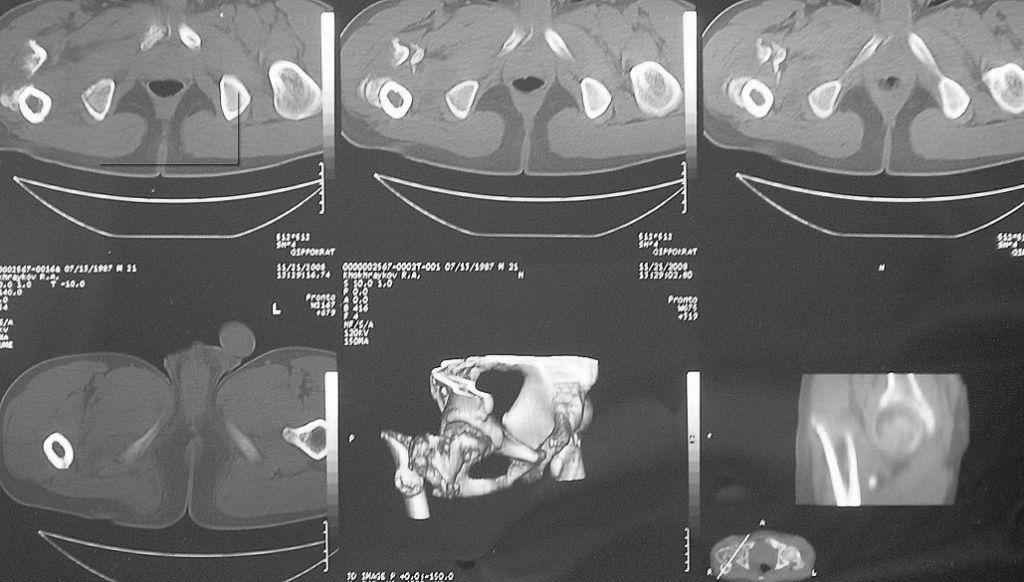

Уважаемые коллеги! Нужен совет. Больной Х., 21 год, ДЗ: ложный сустав вертельной области правого бедра.

Травма 8 мес. назад, ДТП, получил закрытый межвертельный перелом правого бедра. Лечился в городской больнице одного из городов-спутников г. Караганды скелетным вытяжением в течение 3 недель, затем кокситной гипсовой повязкой 2 мес. В настоящее время имеется укорочение конечности на 7 см, умеренная боль в вертельной области; ходит без костылей, полностью нагружая больную конечность, при нагрузке отмечается смещение дистального отломка проксимально примерно на 1,0 см.; объем движений в коленном суставе сохранен; при пальпации отломков боли нет, умеренная патологическая подвижность. Планируем внеочаговый остеосинтез спице-стержневым аппаратом, дистракция до восстановления длины бедра, вторым этапом остеосинтез стержнем Гамма. Есть надежда, что на дистракции пойдет сращение и у больного хватит терпения завершить лечение в аппарате.

Компоновка аппарата: три стержня в центральный отломок на полукольце или сегменте, кольцо с тремя спицами в зоне мыщелков бедра, две из них с упорными площадками; по стержню в конец дистального отломка и диафиз. Нуждаемся в советах: